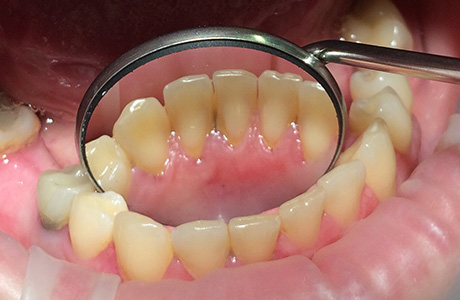

До и после лечения

К нам в клинику обратилась пациентка, которая была недовольна налётом и зубными отложениями. Также она отметила, что зубы со временем приобрели желтоватый оттенок. Специалист Вахлюева Елена Сергеевна после проведённого осмотра рекомендовала пациентке процедуру профессиональной гигиены полости рта.

Очень часто пациенты обеспокоены потемнением эмали, желтизной зубов. Как правило, в таких случаях наблюдаются твёрдые и мягкие отложения на зубах. Мы всегда рекомендуем процедуру, которая легко решает подобные проблемы — профессиональная чистка. Как бы хорошо и качественно вы не чистили зубы в домашних условиях, работа специалиста в этой ситуации необходима!